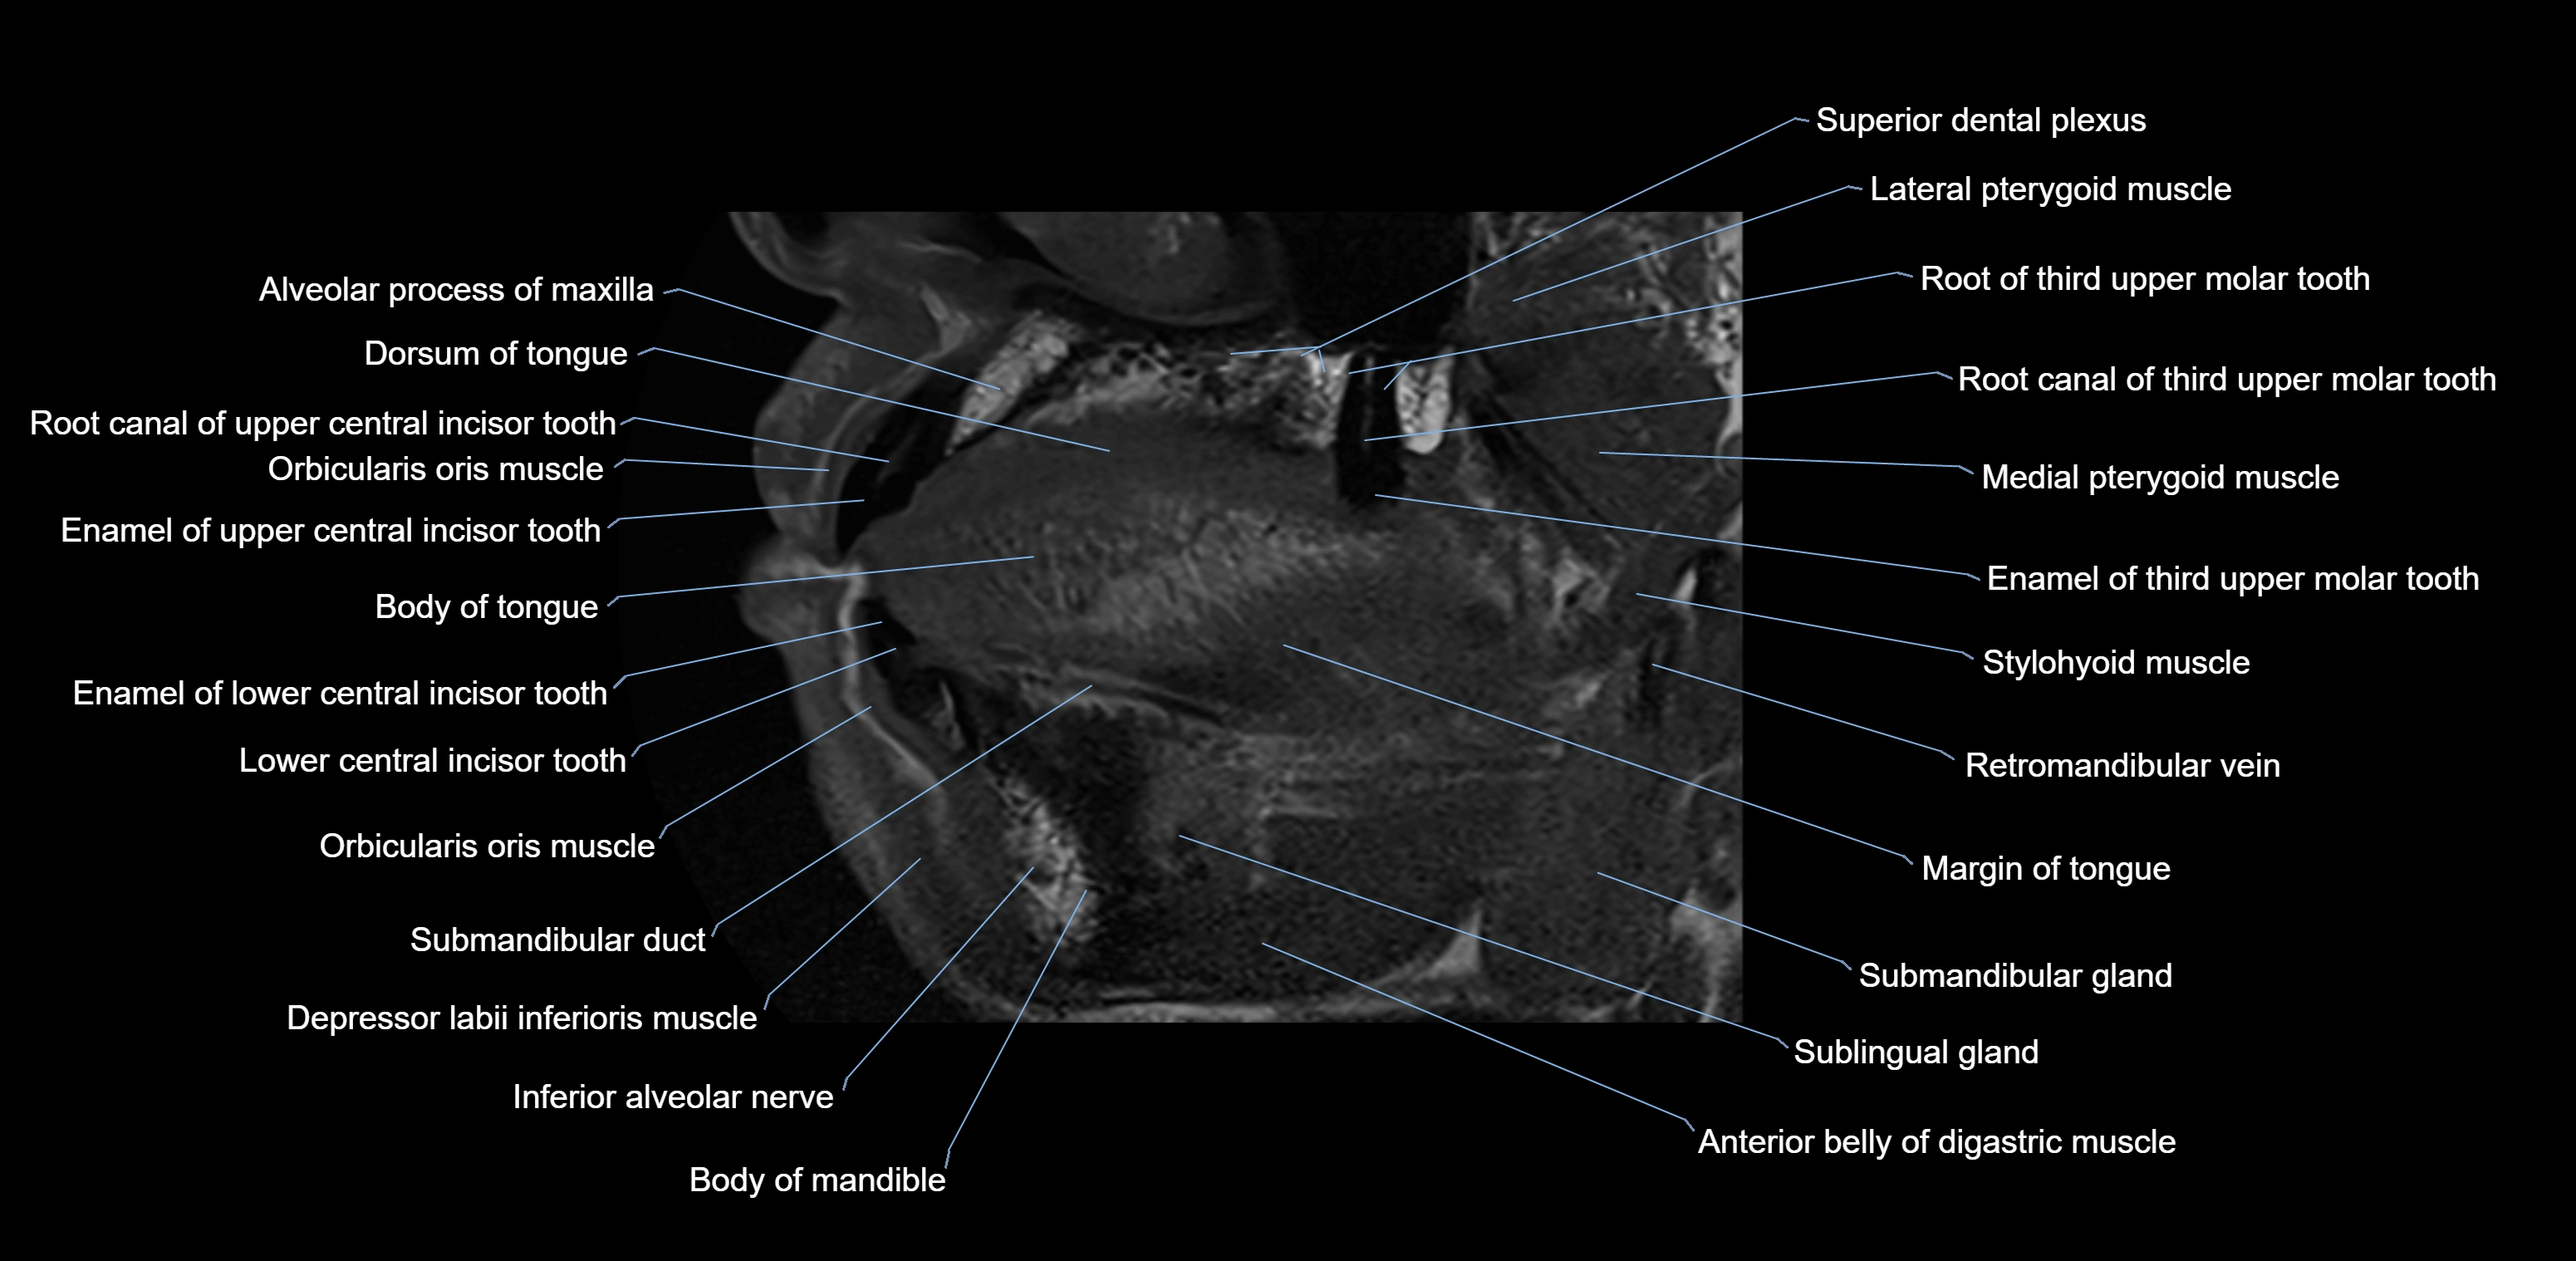

- Body of tongue

- Dorsum of tongue

- Inferior alveolar nerve

- Orbicularis oris muscle

- Body of mandible

- Anterior belly of digastric muscle

- Stylohyoid muscle

- Superior dental plexus